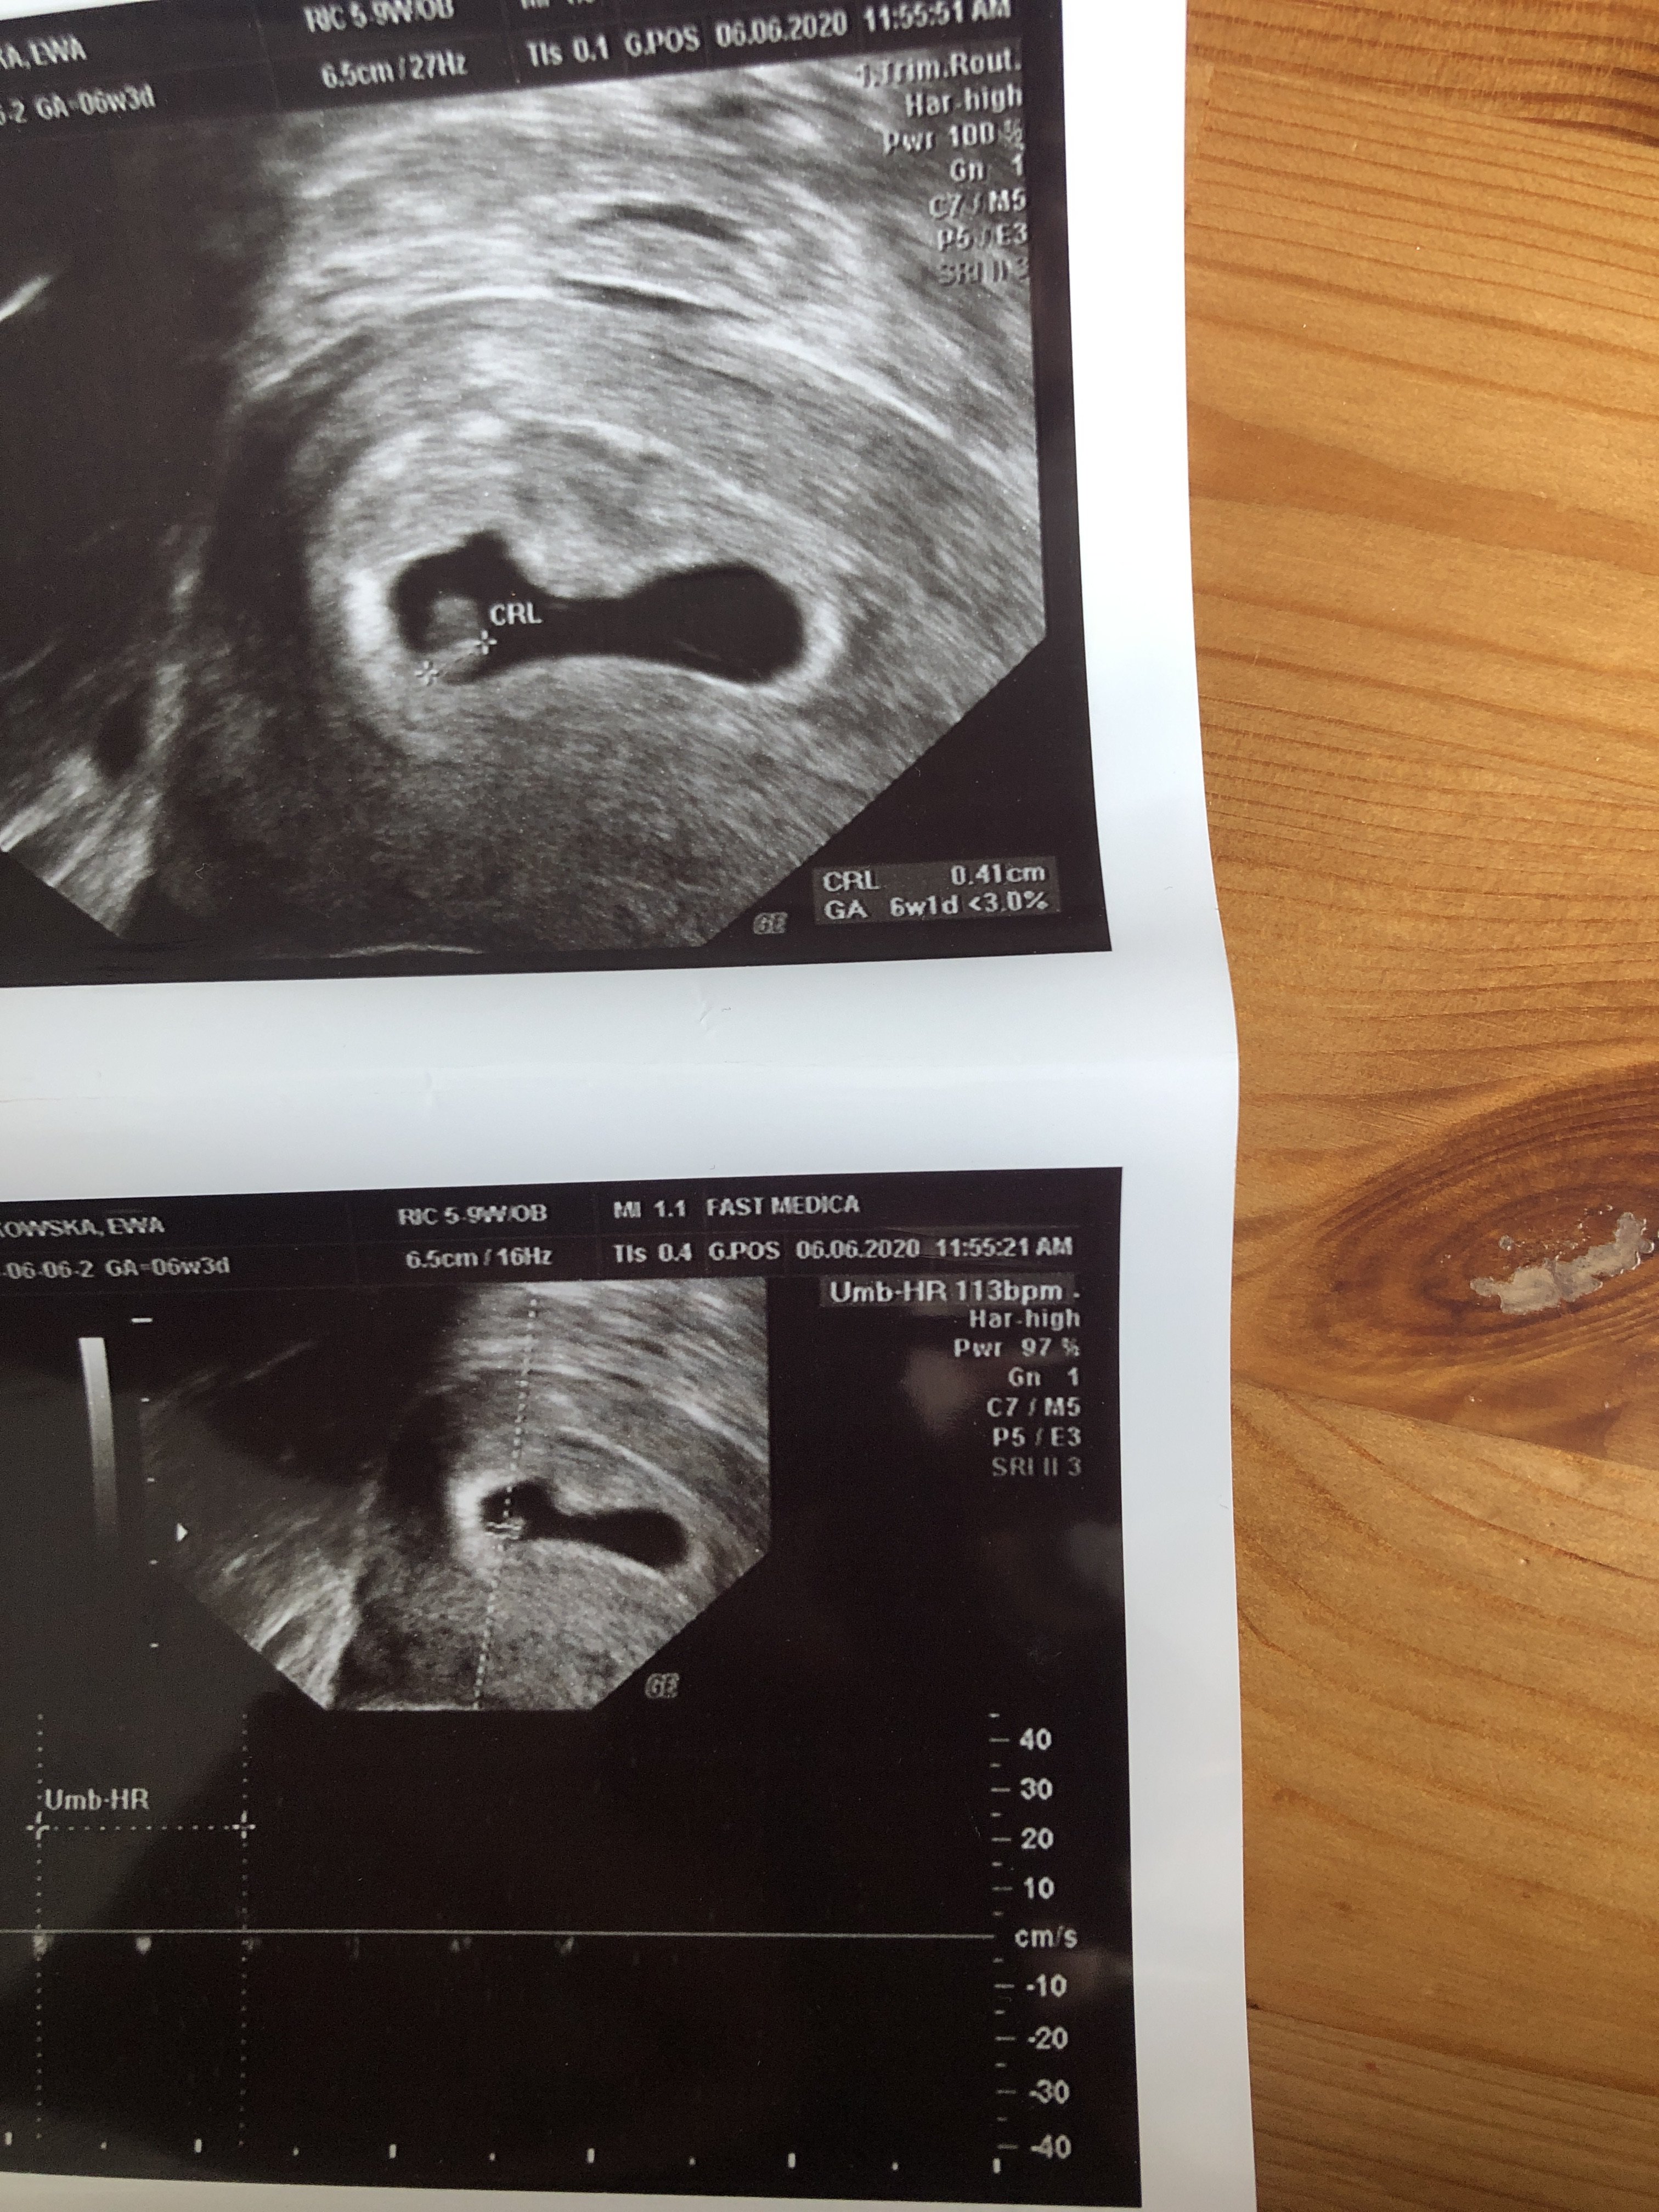

kochane ja już po wizycie dużo stresu według Om 6+3 według usg 6+1

termin porodu na 28 stycznia Srsduszlo bije ❤️❤️ Tylko pęcherzyk trochę spłaszczony dostałam leki na podniesienie progesteronu trochę się tym martwię 😔 i zalecił mi branie acard czy któraś tez bieze

termin porodu na 28 stycznia Srsduszlo bije ❤❤ Tylko pęcherzyk trochę spłaszczony dostałam leki na podniesienie progesteronu trochę się tym martwię 😔 i zalecił mi branie acard czy któraś tez bieze